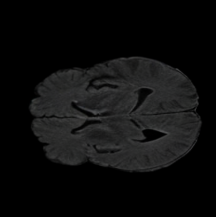

6.3 When does X-Diffusion Fail?

To see when and how X-Diffusion fails, we conducted an experiment on healthy brains (no tumour) using the IXI dataset, by running an X-diffusion trained on the BRATS brain tumor dataset. Our X-Diffusion achieved a PSNR of 35.86 dB on the IXI dataset despite being trained on the BRATS dataset. We then ran the tumour segmenter on the set of 582 healthy scans and corresponding generated MRIs. The segmenter predicted tumours in 9.9% of the real healthy brains and in 11.3% of the generated brain MRIs. Some of these tumor hallucination examples from X-Diffusion generation are shown in Figure 9.

This shows how the generated MRIs indeed preserve the tumour information and can act as an affordable and informative pseudo-MRI, before conducting an actual costly MRI examination in hospitals. Given that our model has been trained on brain scans all with tumours, we expect to see hallucinations of tumours in healthy scans. We report two cases of failure of our model in Figure 16. Hallucinations of tumours on healthy samples represent 2% of the test set.